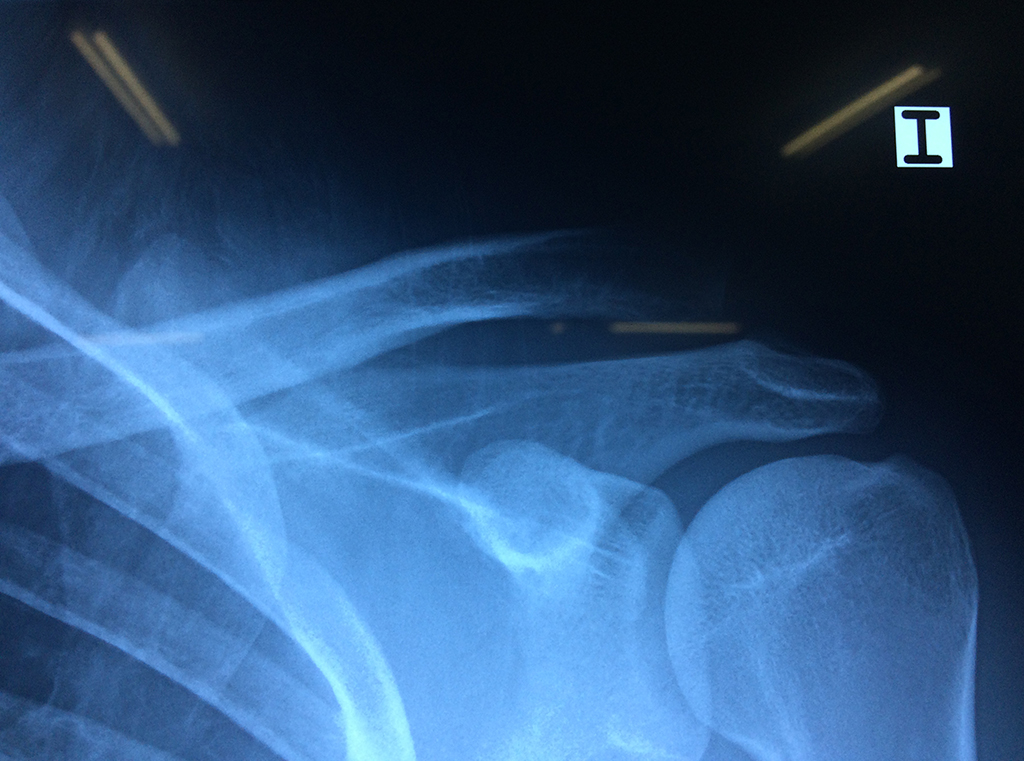

La principal articulación del hombro es la que une la cabeza del húmero con la escápula, recibe el nombre de articulación escapulohumeral y presenta dos superficies articulares, una de ellas corresponde a la cabeza del humero que tiene forma semiesférica y la otra es la cavidad glenoidea de la escápula, estas superficies están recubiertos por cartílago que permiten un movimiento suave e indoloro.

Exteriormente una envoltura de tejido blando circunda el conjunto, es la llamada cápsula articular que está reforzada por varios ligamentos que le dan estabilidad e impiden que los huesos se desplacen más allá de sus límites fisiológicos. Un conjunto de músculos y sus tendones se unen a las superficies de los huesos y hacen posible la movilidad de la articulación, entre ellos es muy importante el manguito rotador formado por cuatro músculos que proporcionan movilidad y estabilidad al hombro.

Varias estructuras transparentes en forma de saco llamadas bolsas serosas, permiten el deslizamiento suave de los diferentes componentes móviles. El hombro es la articulación con mayor amplitud de movimientos del cuerpo humano.